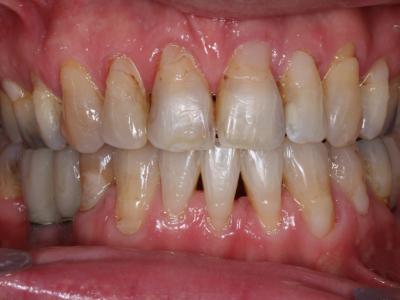

Sur le plan parodontal, le contrôle de plaque insuffisant et l’accumulation importante de tartre sur l’ensemble des dents maxillaires et mandibulaires entraînent une gingivite étendue. Des récessions importantes sont également visibles. Les sondages ne relèvent quant à eux aucune poche parodontale ni perte osseuse notable. La formule dentaire indique l’absence de 36, 45, 46, non remplacées, l’absence de 15, 25, 31, avulsées étant plus jeune pour créer de la place en vue du traitement orthodontique et celle de 28, 38 étant sans antagoniste.

Une classe 1 d’angle, une hyperdivergence faciale et une endognathie maxillaire sont diagnostiquées grâce à l’analyse céphalométrique. Sur le plan alvéolaire, une classe 2 molaire, une classe 3 canine (par la perte de 31), une infraclusie incisive ainsi qu’un encombrement maxillaire et mandibulaire sont à observer. Certains soins méritent d’être repris par perte d’étanchéité. En outre, pour des raisons purement esthétiques, le patient désire remplacer tous ses amalgames dentaires.